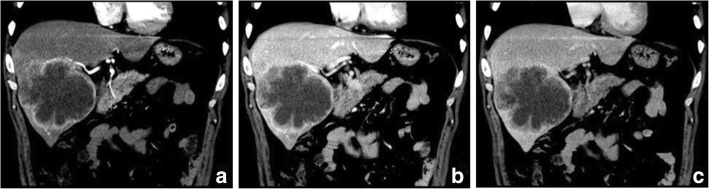

Fig. 3.

Sarcomatous hepatocellular carcinoma in a 56 year-old man. The heterogeneous mass with a large area of cystic change exhibits rim enhancement on the arterial phase (a) with a slight progression towards the center on the later phases (b, c)

Regarding the distribution of enhancement, peripheral enhancement was seen in 2 S-ICCs and 3 S-HCCs (Fig. 3). Mix rim and internal heterogeneous enhancement (Fig. 4) was found in 2 S-HCCs, internal heterogeneous enhancement was shown in 2S-HCCs and 1 S-HCC–CC (Fig. 6), and no homogeneous pattern was observed. Eight tumors including 2 S-ICCs, 5 S-HCCs and 1 S-HCC–CC were hypo-vascular (Figs. 1, 2, 3 and 4) and the remaining 2 S-HCCs mainly presented hyper-intense enhancement on the arterial phase. As to the enhancement degree of the solid part in the tumor, six tumors showed hyper enhancement compared to the background liver.

With respect to the dynamic pattern of enhancement, of the ten tumors, 40% with 2 S-HCCs and 2 S-ICCs showed peripheral enhancement on the arterial phase and progressive enhancement towards the center (Fig. 2) on the later phases, 20% with 2 S-HCCs showed heterogeneous enhancement on the arterial phase and progressive or persistent enhancement on the later phase (Figs. 2, 3, 4 and 5), and 30% with 3 S-HCCs presented obvious peripheral and heterogeneous enhancement on the arterial phase and then wash out peripherally and partially on the later phase, mimicking ordinary HCC. The remaining S-HCC–CC exhibited a variable enhancement character for its multinodular change (Fig. 6). The tumor showed mild inhomogeneous enhancement on the arterial phase, and the portion near the subcapsular area of the tumor showed persistent thin rim enhancement accompanied by an mural nodular on the portal and equilibrium phase, next to the cyst change was the mild to moderate progressive fill-in enhancement, and the upper portion presented washout on the equilibrium phase.

Our study demonstrated that PHSC generally presented hypovascularity seen as peripheral enhancement on the arterial phase imaging. The PHSC was characterized by the peripheral viable cancerous tissue with fibrous stroma and central necrosis or hemorrhage [14, 26]. Similar to prior results [6, 15], the necrosis was more frequently seen with a high frequency of 85.7% (six of seven) in the surgically resected tumors in our study. The poorly differentiated cells of the sarcomatoid component grew so rapidly that the neovasculature could not adequately supply the fast-growing malignant cells, resulting in the central necrosis. In additional to the peripheral ring enhancement, when the necrosis was accompanied by fibrous septum or was scattered, the tumors might exhibit heterogeneous enhancement distribution such as a mix of rim and internal or internal only heterogeneous enhancement as shown in our study.